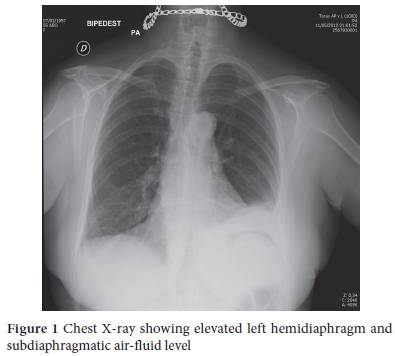

A 55-year-old patient presented to the emergency department with a 48-h history of pain in the lower left hemithorax with pleuritic characteristics. Two days before she experienced vomiting and diarrhea. At arrival, she complained of moderate pain in the left lower hemithorax. The pain was characterized as dull, constant, radiating to the left upper abdominal quadrant, aggravated by body posture changes without any alleviating factors, and accompanied by nausea and low-grade fever. Her medical history was unremarkable except for previous appendectomy. The patient did not take any medications, and she was not a smoker or an alcohol consumer. She looked ill with a blood pressure of 123/88 mmHg, a pulse rate of 84 beats/min and a temperature of 38.5°C. A thorough physical examination revealed hypoventilation in the left lower base without other relevant findings. The laboratory examination was unremarkable except for polymorphonuclear leukocytosis (total leukocyte count, 18000/mL; neutrophils, 86%) and an elevated C-reactive protein (86 mg/dL; reference range, 0-5). An upright chest radiograph demonstrated elevation of the left hemidiaphragm and free gas under the diaphragm (Fig. 1).

Laboratory examination is not helpful, hemogram usually demonstrates leukocytosis with a left shift. Changes in acute phase markers (elevation in C-reactive protein and erythrocyte sedimentation rate; decrease in albumin) may also be seen. The rarity of this disease and its nonspecific presentation make early diagnosis difficult. Plain abdominal X-rays are abnormal in 50% of cases and findings include paralytic ileus, edematous gastric folds, elevation of the left hemidiaphragm and free gas under the diaphragm. Upper gastrointestinal series may show a filling defect suggestive of submucosal mass. On CT, the lesion appears as a localized area of mural thickening within the stomach wall, while fluid and air may also be seen within the mass [8]. Intramural gastric abscess is diagnosed with increasing frequency by endoscopic ultrasonography [2,3,9]. On ultrasound, it appears as a well-defined hypoechoic mass within the gastric wall with increased vascularity around the mass on the color Doppler images [1]. Although the ability of EUS to evaluate phlegmonous gastritis is not established it may be helpful in differential diagnosis as it is the best examination to delineate the gastric wall. The recommended therapy for an intramural gastric abscess is surgical drainage in combination with antibiotics. However, technical advances now allow both radiologic and endoscopic intervention. Antibiotics are the mainstay of treatment. Drainage, surgical or endoscopic, is helpful and occasionally necessary and may reduce hospitalization time [2,3,9,10].